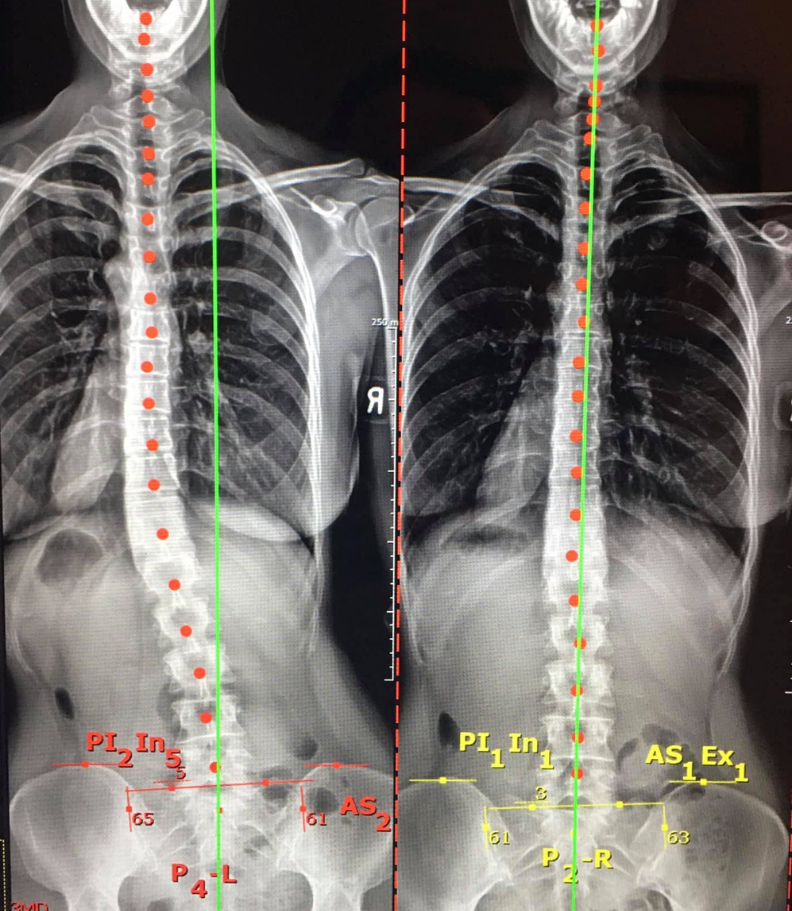

Chiropractic care for disc injuries in Glastonbury, CT has a well-established track record of delivering both immediate pain relief and the potential for long-term recovery. The treatment process involves a comprehensive evaluation of your medical history, x-rays, and a physical examination to gauge the extent of the disc injury and determine the appropriate course of action.